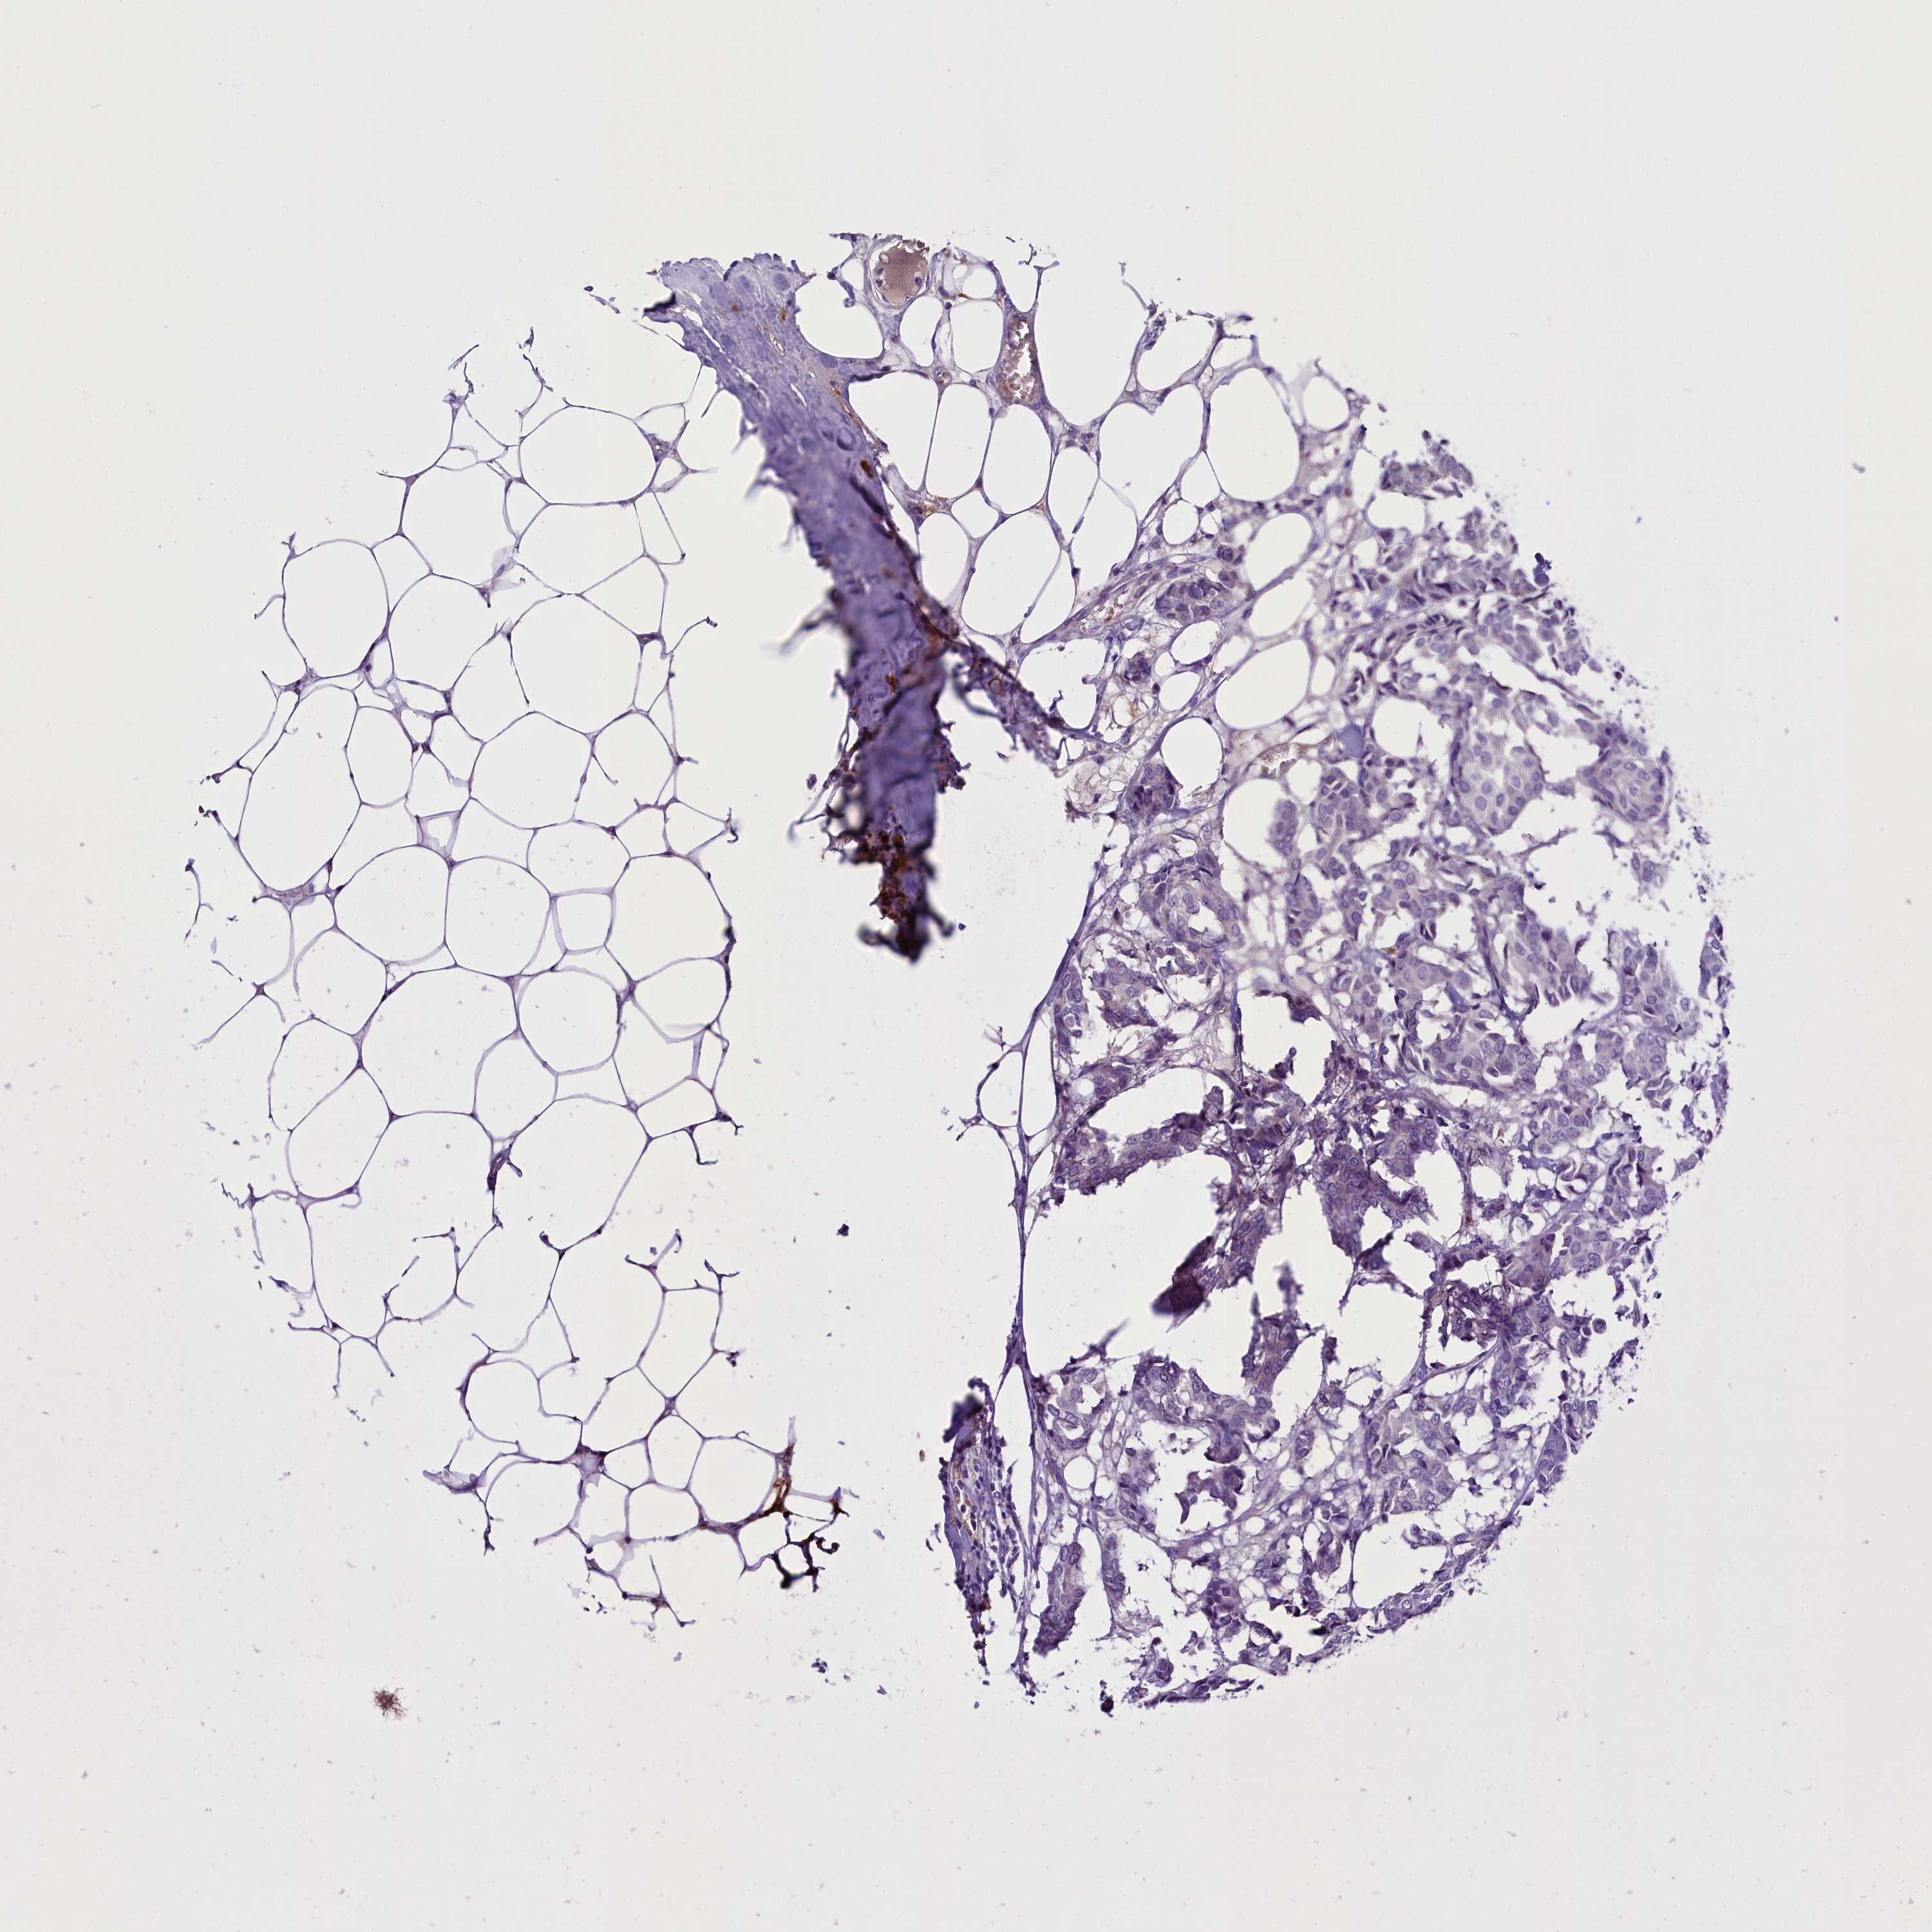

CANCER BREAST CANCER Show tissue menu

BRCA TCGA BRCA VALIDATION PROTEIN EXPRESSION

ANTIBODIES

AND

VALIDATION